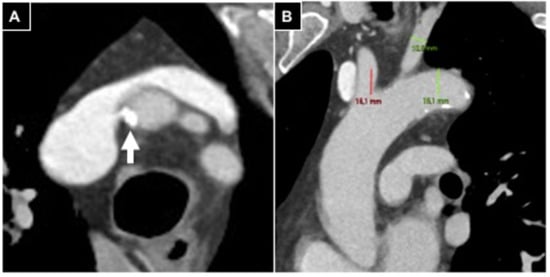

- Iezzi, R.; Posa, A.; Contegiacomo, A.; Maresca, A.; Rodolfino, E.; Merlino, B.; Bilhim, T.; Guimaraes, M. Application and Validation of a transRADial Access Score (RAD-Access) in Patient Selection for Safe Radial Access in Liver Cancer Intra-Arterial Procedures. Cancers 2025, 17, 1385. [Google Scholar] [CrossRef]